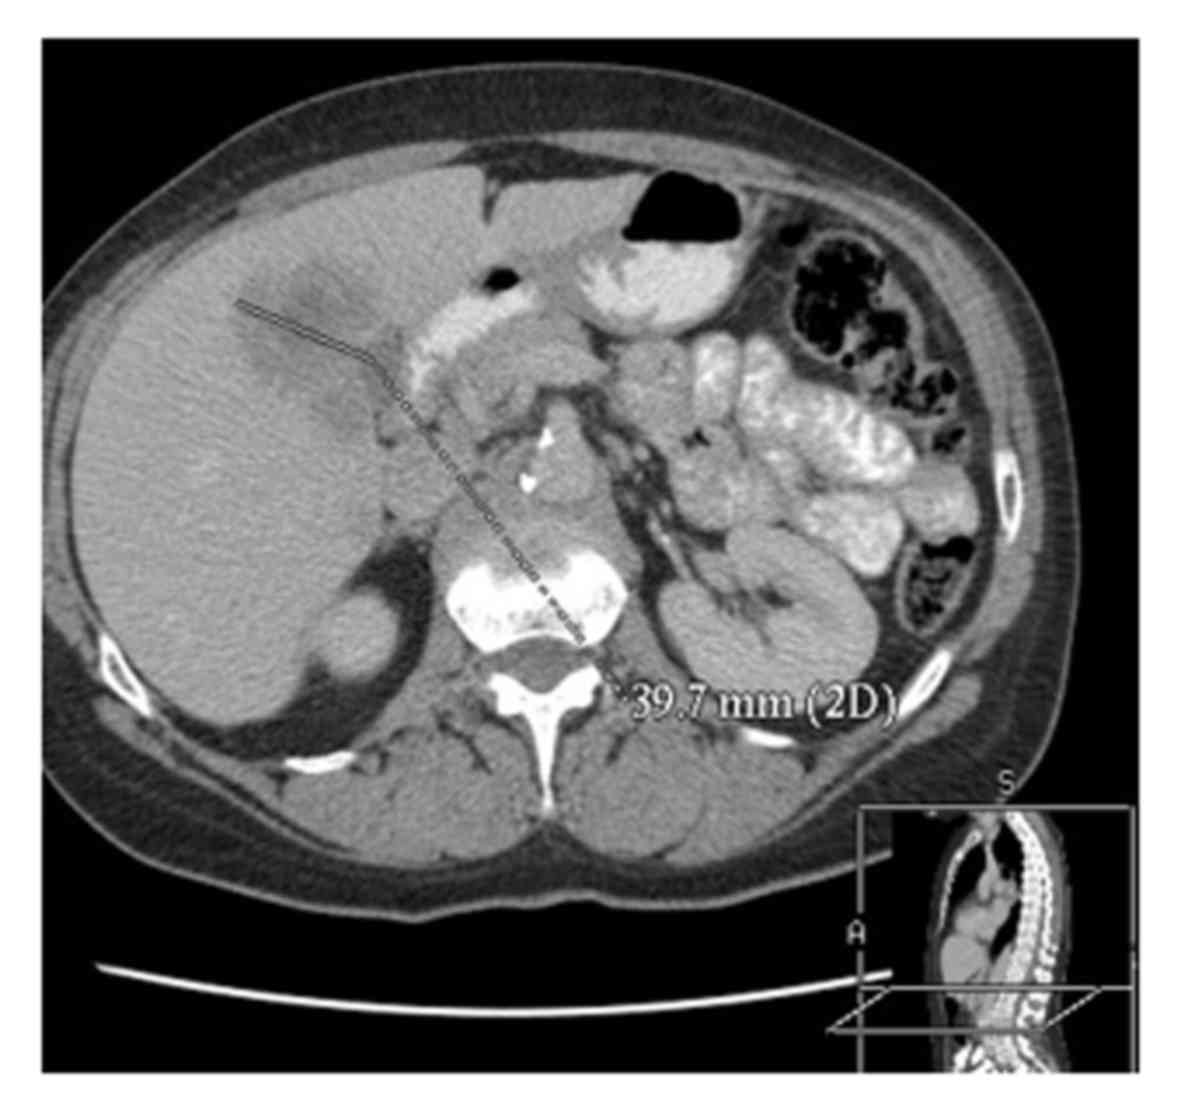

In February 2011, a 62-year-old woman was diagnosed with SCLC (Figs. 1 and 2). The patient was a retired teacher and a smoker (20 cigarettes/day for 45 years).A chest X-ray followed by computed tomography were performed to explain the cause of a persistent cough following a respiratory infection~1 month earlier. The diagnosis of SCLC was based on microscopic examination of the material obtained during bronchoscopy. The patient's overall health was good, but she reported previously taking metformin due to impaired fasting glucose and atorvastatin due to hypercholesterolemia. At 5 weeks after the initial diagnosis, chemotherapy with platinum (49.69 mg/day for 3 days) and etoposide (165.62 mg/day for 3 days) was administered. The patient received 6 cycles of this treatment, but the intervals between cycles had to be prolonged due to leukopenia (WBC <2,500/µl). Cancer remission was achieved after 6 cycles of standard therapy. After the 4th cycle, PCI (2.5 Gy/g; 10 cycles) was performed. In addition, long-term enoxaparin (40 mg/day) therapy lasting 2 years was prescribed.

Figure 1.

Computed tomography imaging showing the lung tumour at the time of diagnosis.